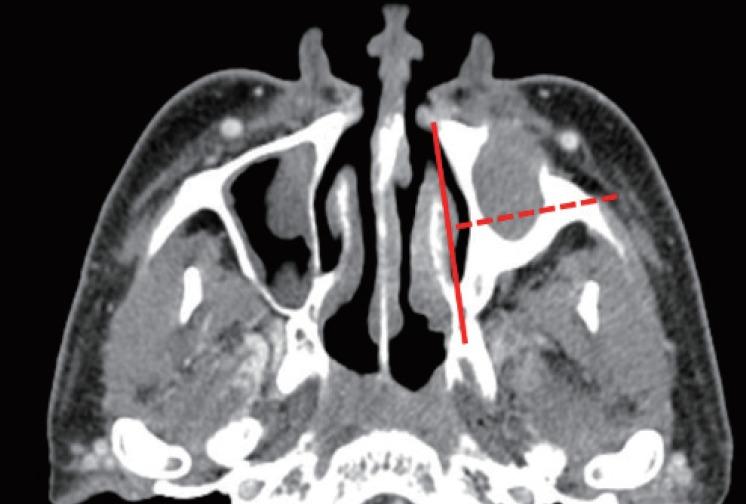

Postoperative cheek cyst (POCC) is a late postoperative complication of radical maxillary sinus surgery including the Caldwell-Luc (C-L) operation. The present study aimed to evaluate the therapeutic outcomes of surgical treatment for POCC and to assess the clinical factors correlated to these outcomes.

This study included 57 patients (67 nostrils) diagnosed with POCC who underwent surgical drainage. The medical records of the patients were retrospectively reviewed for radiological findings, treatment modalities, residual symptoms, and recurrences.

In total, 30 patients were male and 27 patients were female with a mean age of 55 years, and the patients were usually diagnosed with POCC 28.2 years after radical surgery. Endonasal endoscopic marsupialization was performed via inferior meatal antrostomy, and if possible, middle meatal antrostomy was performed at the same time. In patients with cysts that were difficult to reach using an endonasal endoscopic approach, additional open C-L approaches were performed. The median follow-up period was 19.4 months. Overall, adequate drainage and symptomatic relief were achieved in 91% (61/67) of the patients. The recurrence rate was significantly higher in patients who had anterolateral POCC. Failure to achieve symptomatic relief was correlated to a smaller cyst and the use of the open C-L approach for drainage.

The location and size of the cyst as well as the use of the open surgical approach were important factors in predicting the therapeutic outcome of POCC. The time point of treatment and surgical approaches should be based on the above-mentioned findings.